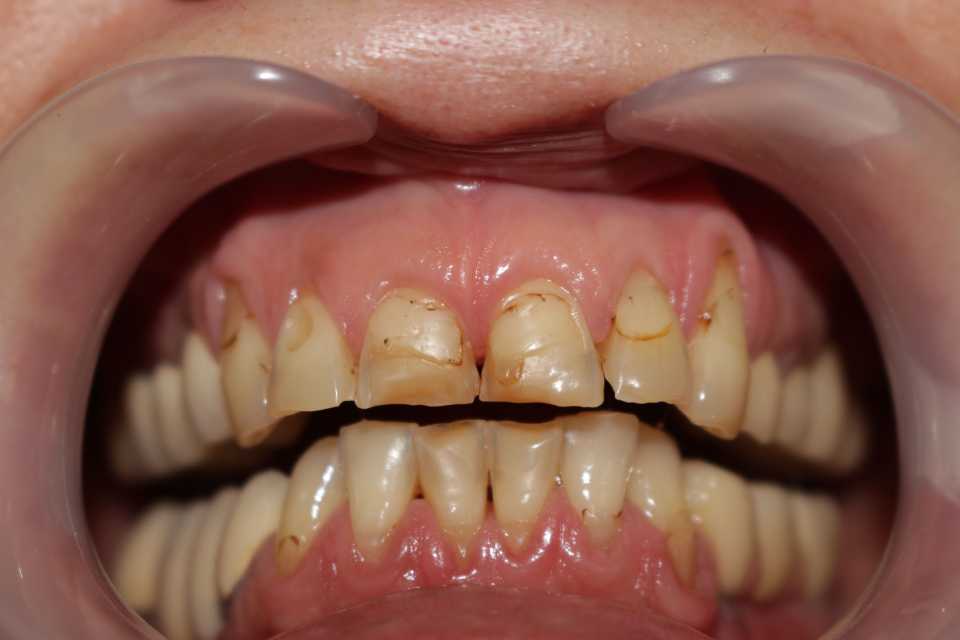

Poza inițială relevă obturatii nefizionomice, cu un compozit imbatranit ce prezinta la interfata cu dintele discromii exogene. De mentionat este si faptul ca toti dintii sunt vitali.

Cazul a fost rezolvat cu ajutorul coroanelor de tip ceramică pe suport de zirconiu, in 2 sedinte, cu slefuiri minim invazive, dintii ramanand vitali.